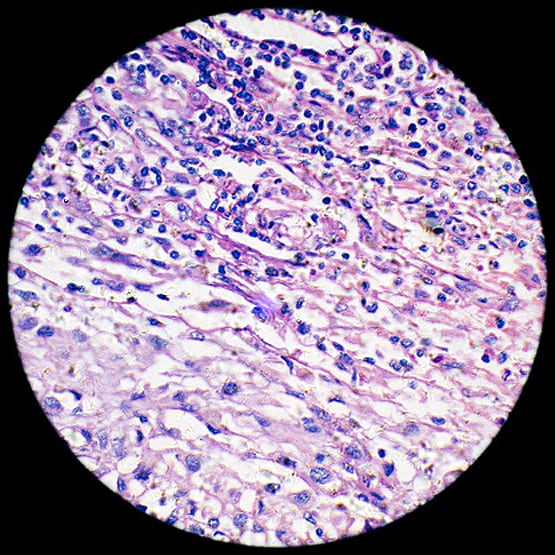

दोनों डॉक्टरों ने बताया कि इस महिला को टेस्टीक्यूलर कैंसर (Testicular Cancer) है. जो पुरुषों को होता है. ये महिला जिस दुर्लभ स्थिति में है, वह 22 हजार लोगों में से किसी एक को होता है.(प्रतीकात्मक फोटोः गेटी)

इस महिला में पुरुषों के अंडकोश हैं. जो उसके शरीर के अंदर हैं. उसमें कैंसर हो गया है. टेस्टीक्यूल कैंसर को सेमिनोमा (Seminoma) भी कहते हैं. इस महिला के पास आम महिलाओं की तरह सभी जननांग हैं, लेकिन वो गर्भवती नहीं हो सकती. (प्रतीकात्मक फोटोः गेटी)